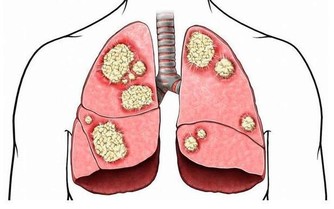

想要胃好好的,除了要改掉上述的惡習,還要及時發現胃的“委屈”,緩解胃的“傷害”,否則等到胃癌來敲門,就晚了。

如果你經常出現下面幾種情況,最好考慮做一下胃鏡檢查。

1. 反复腹痛,尤其是上腹部脹痛不適

上腹部脹痛不適、噯氣、食慾不振、消化不良、進食後異常飽脹,甚至在吃了少量食物後,也莫名的飽,這些是早期胃癌最常見的症狀。

2. 貧血、大便發黑

胃癌可導致胃部出血,因此人會出現貧血、便血、大便發黑的症狀。

3.有明顯的消化道症狀,如經常嘔吐、厭食、反酸、噯氣、上腹飽脹等。

胃癌會減弱胃的蠕動功能,造成進食後胃酸可能隨著食物反流回食道,引起燒心、反酸。

4. 短期內暴瘦

胃里長有腫瘤,不僅會影響食慾和正常進食,還會導致食物分解不當,影響吸收。

如果短期內暴瘦,比如一個月就減了10斤,不要因為減了些肉而高興,要當心是否被胃癌或其他惡性腫瘤盯上。